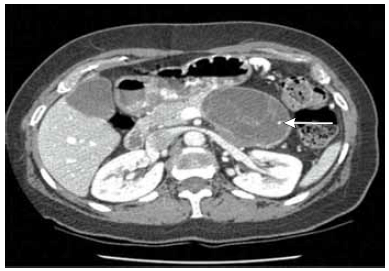

Mulher de 52 anos procura atendimento médico com queixa de dor abdominal há 10 meses, de fraca intensidade, sem relação com alimentação e ausência de alteração do hábito intestinal. Na investigação de seu quadro, solicitou-se tomografia abdominal, demonstrada a seguir (lesão apontada pela seta). Realizada punção aspirativa com agulha fina, cujo resultado demonstrou aspirado rico em mucina, níveis elevados de CEA e estroma similar ao do ovário.